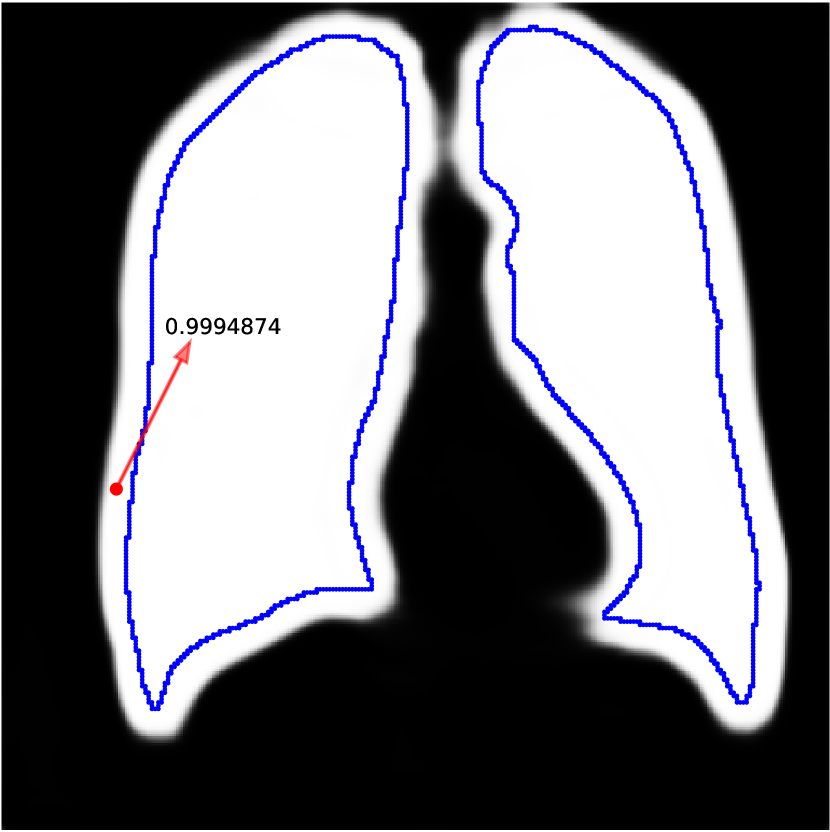

Network predictions can be over confident if bias shows up in training labels. Some works (Zhang et al., 2020b; Li et al., 2021) choose to trust the network prediction probability to correct label noises, i.e. they believe predictions with small confidence is likely to be wrong while pixels with large confidence tend to be correctly predicted. However, the network can fit to noisy labels quickly and be overconfident when trained with biased noisy labels. This phenomenon is also observed by Zhang et al. (2016). In Figure A.3(a), we train a network with dilated noises and show its prediction probability map, i.e. the output after sigmoid. The red pixel is predicted as foreground with a high probability , whereas it is actually in background. Therefore, methods based on trusting the network predictions cannot correct this label because the network is over confident. And since the network can fit to noise rapidly, early learning techniques also cannot eliminate this bias. Our method works because we do not trust the network prediction. Instead, we compare it to the clean label in validation set and estimate the bias. We then eliminate this bias in the training prediction. We also show how the prediction probability changes while training the model in Figure A.3(b). It shows that the model can be over confident quickly while training. So methods that employ early learning techniques (Liu et al., 2020; Arpit et al., 2017; Liu et al., 2022) are hard to work under biased noisy labels.